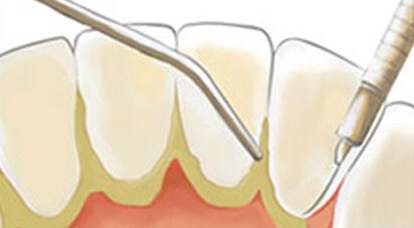

洗牙之后牙縫會變大嗎?實際上這個是犯了邏輯錯誤問題。不是洗牙導致牙縫變大的,而是洗牙時把牙縫中的牙結石去掉了,因此你感覺牙縫中變空變大了,這是因為牙縫本來就被牙結石占據導致變大的。

本來我們的牙齒牙縫是很小的,牙齒都緊挨著,但是慢慢地,因為有時一些食物殘渣殘藏在牙縫中,刷牙也難以全方位、無縫隙的清除到位,久而久之形成了牙結石,而當我們把這些牙結石去掉之后,原本牙結石的位置空了,就會顯得牙縫特別大。

其實,洗牙的好處就是把你牙縫中的牙結石清除干凈,預防口腔疾病,而牙結石,通常是很硬的,一旦形成,即使你刷牙也刷不掉。